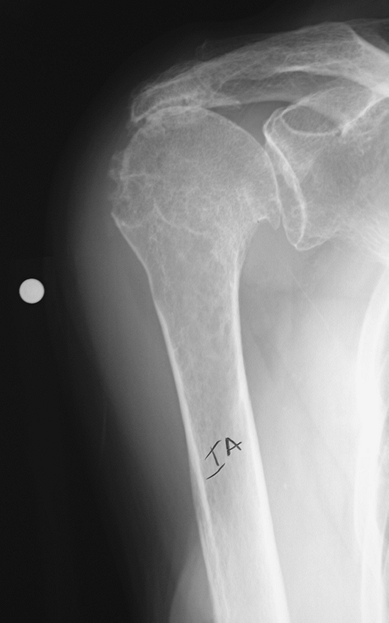

Figure 42-3

True anterior posterior radiograph of a shoulder with a chronic massive rotator cuff tear. Although, there is reduction of the acromial humeral space and the humeral head is elevated relative to the glenoid, there is no glenohumeral arthritis. |

of five plain radiographs. These views include a true anteroposterior,

patients with chronic massive rotator cuff tears (Fig. 42-3).

and narrowing of the acromiohumeral space are findings that are

consistent with long-standing rotator cuff pathology (Fig. 42-4).

It has been suggested that an acromiohumeral space <7 mm is

consistent with a rotator cuff tear and that when the space is <5

mm, there is a massive tear. Erosion or rounding off of the greater

tuberosity (femoralization) is typical of long-standing massive rotator

cuff tearing. Similarly, long-standing contact of the greater

tuberosity with the acromion can lead to the formation of a facet on

the underside of the lateral acromion as well as spurring and

excrescences on the greater tuberosity that can be visualized on

anterior posterior radiographs. The true anteroposterior and axillary

lateral radiographs can also demonstrate glenohumeral arthritis. The

axillary lateral view also demonstrates the relative anteroposterior

position of the humeral

head.